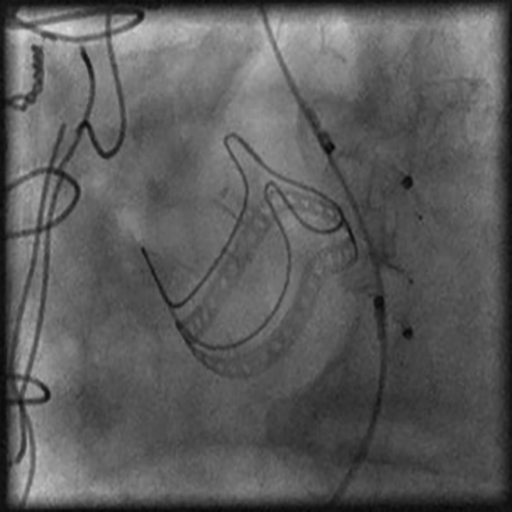

After one month, valve-in-valve TAVI using a Lotus 23 mm valve was performed. The use of a fully repositionable device was helpful to check final gradients before final valve release and obtain the best final position.